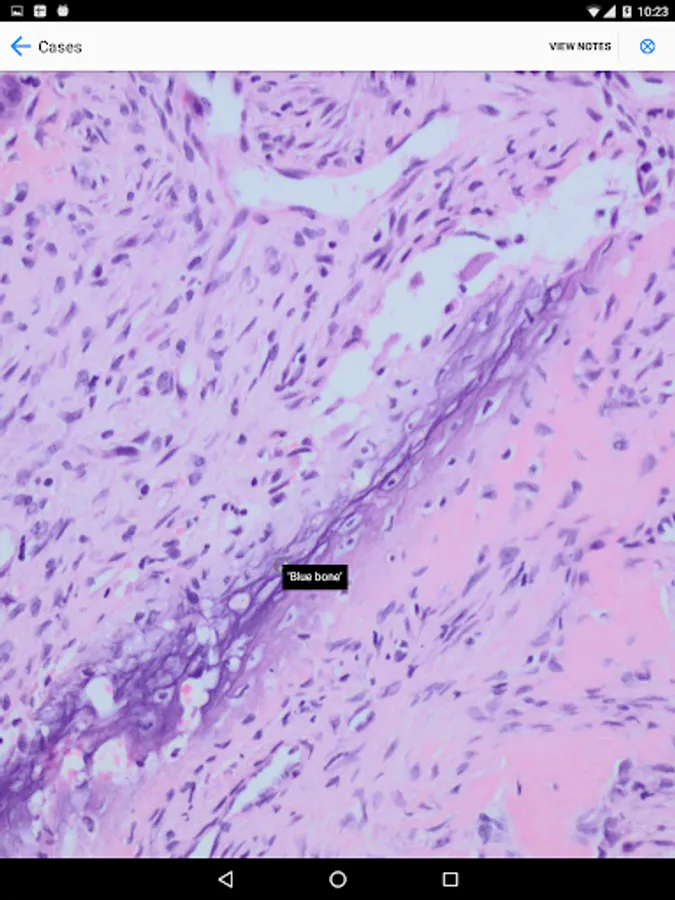

BoSTT brings the user a real experience of frequent and rare, typical and more unusual cases of bone and soft tissue tumours. Each case has a clinical history, high resolution radiology and pathology images, diagnosis, treatment and learning points.